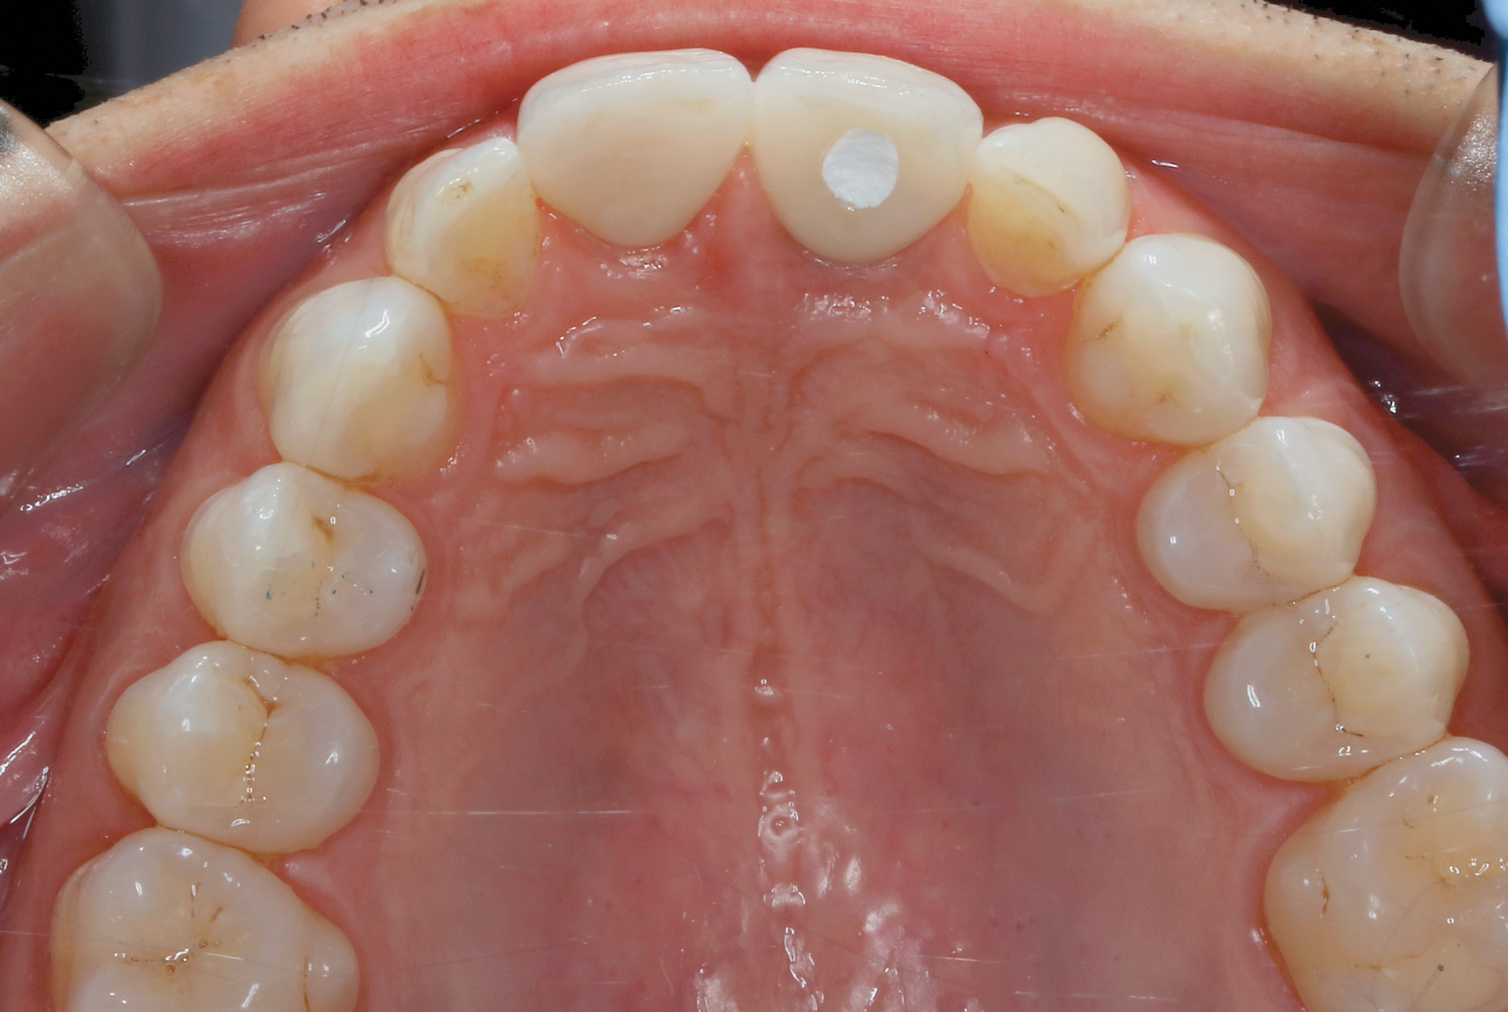

Fig 6. Incisal view (clinical) of implant-retained crown demonstrating ideal position of access opening in the cingulum using the angulated screw channel.

Figure 6